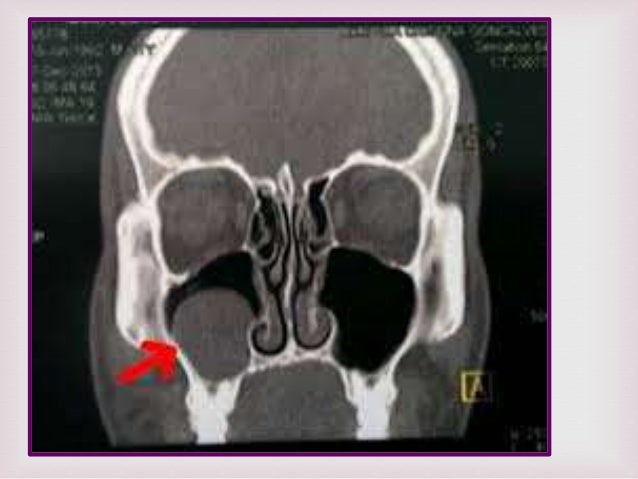

TOMOGRAFIA AXIAL COMPUTADA Y CONE BEAM

Tomografía